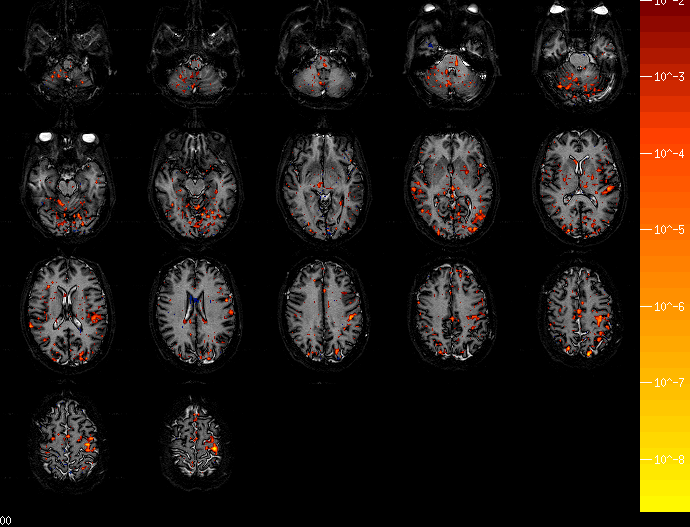

• Nestor's Brain Tracking a Motor Sequence with Prior Info ,

various horizontal slices.

• Nestor's Brain During "Practeach" Condition in Gary's Experiment ,